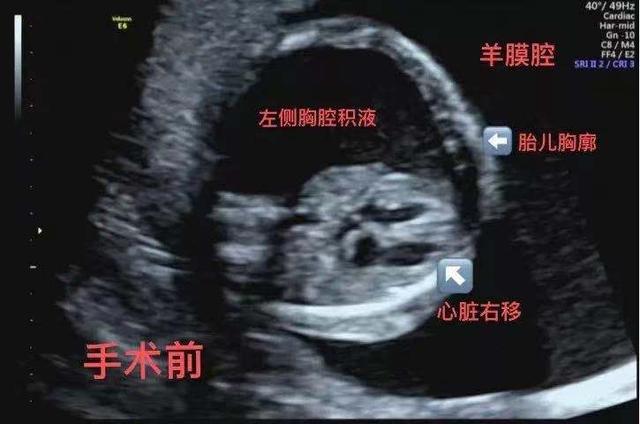

在武汉产检时,陈女士的医生告诉她,“情况不太乐观,胎儿左胸有大量胸水,左肺发育不良,心脏明显向右压。”如果不治疗,这个胎儿很快就会因为心脏和肺部受到严重压力而出现全身水肿和胎儿在子宫内死亡。

虽然刘子健教授因为疫情原因暂时不能来深,但他每天都通过远程诊疗系统了解胎儿的变化,指导产妇和胎儿团队对胎儿进行严密观察和检查。在评估和等待结果的过程中,胎儿胸腔积液迅速加重,胎儿全身皮肤水肿很快出现,手术迫在眉睫。